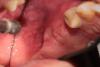

Dio Опубликовано 8 ноября, 2013 Автор Поделиться Опубликовано 8 ноября, 2013 И так уважаемые коллеги, нос дышит, температуры, нет, жалоб по сути нет.Объективно, фибринозный налет в области 28 з. при промывании фиксирован не уходит, в области 28,27 зубов с вестибулярной стороны, апикальнее визуализируется экзостоз, если точнее часть края аутоблока, шаровидным алмазным бором подравнял, фото уже когда подравнял (фото вдвоем не получалось, втроем хоть так получилось) вновь извиняюсь за фото. буду продолжать наблюдать, следующий осмотр 11.11.13. Есть ли у Вас мнения по произошедшему, ответы вплоть руки растут не оттуда принимаются без проблем, но просьба аргументировать, т.к. меня волнует анализ, для того чтобы не наступать на одни и те же грабли.... Ссылка на комментарий

Dio Опубликовано 8 ноября, 2013 Автор Поделиться Опубликовано 8 ноября, 2013 ещё одна.... Ссылка на комментарий